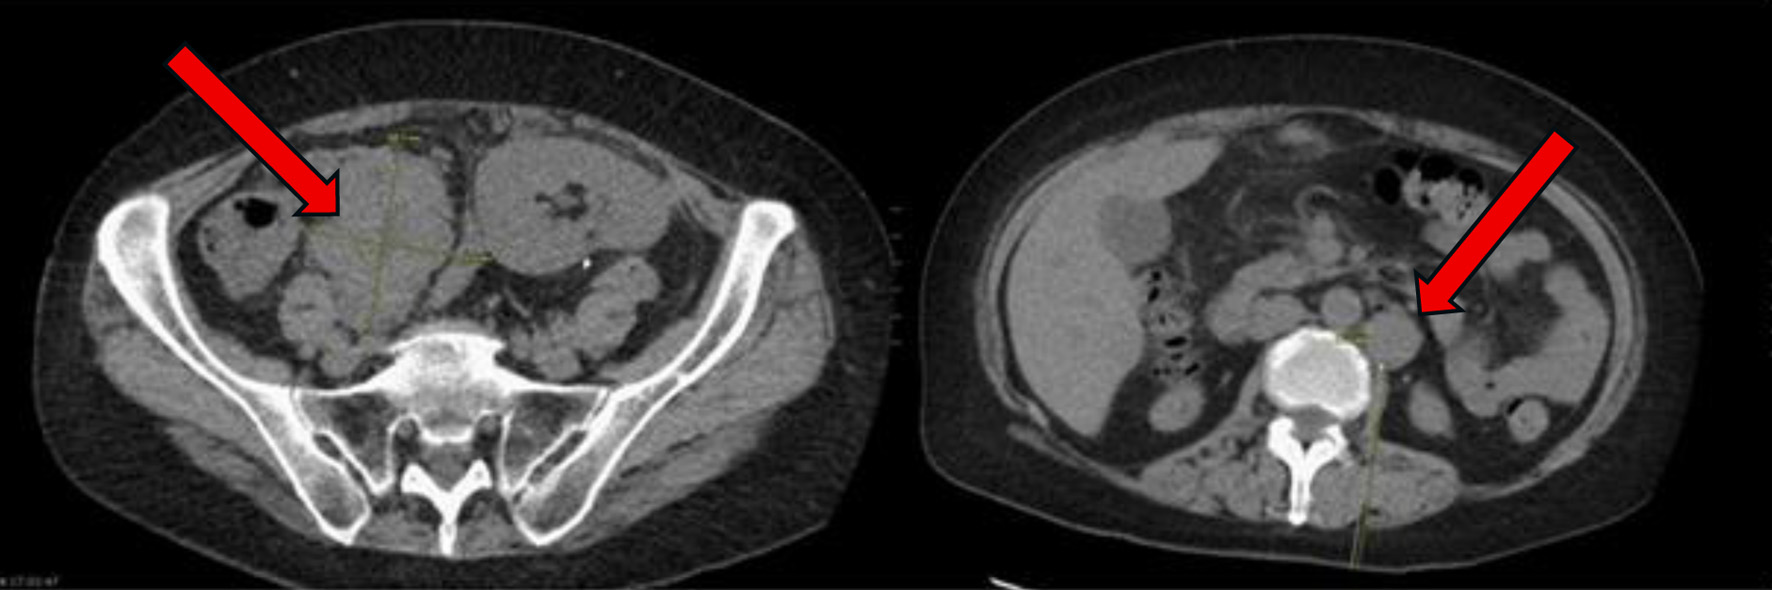

A 57-year-old woman with a history of end-stage renal disease (ESRD) due to IgA nephropathy underwent renal transplant from her sibling. She was placed on standard immunosuppressive therapy with tacrolimus 1 mg twice daily, mycophenolate mofetil 750 mg twice daily, and prednisone 5 mg daily. Nearly 2 years after transplant, she began to develop progressive abdominal discomfort, early satiety, and unintentional weight loss. These symptoms continued to progress over the next 6 months, thus leading to her presentation 30 months after transplant. On the initial examination, she had no overt lymphadenopathy or fever. Laboratory tests showed a white blood cell count of 11.07 × 103/µL, hemoglobin of 10.3 g/dL, and platelet count of 568 × 103/µL. Kidney function remained stable with a creatinine of 0.9 mg/dL, sodium of 139 mEq/L, and potassium of 4.1 mEq/L. Liver function testing was notable for an aspartate aminotransferase (AST) of 50 U/L, alkaline phosphatase (ALP) of 275 U/L, and albumin of 3.4 g/dL. The patient underwent a computed tomography (CT) scan of the abdomen and pelvis, which revealed multiple enlarged mesenteric lymph nodes, liver lesions, and thickening of the terminal ileum (Fig. 1). Notably, the liver mass was heterogeneous and fludeoxyglucose-18 (FDG)-avid on positron emission tomography (PET) scan. Given the concern for malignancy, a retroperitoneal lymph node biopsy was performed.

Figure 1. At time of initial presentation, CT abdomen and pelvis showing increase in size of the abdominal and pelvic lymph nodes (arrows) suspicious for post-transplant lymphoproliferative disorder. CT: computed tomography.